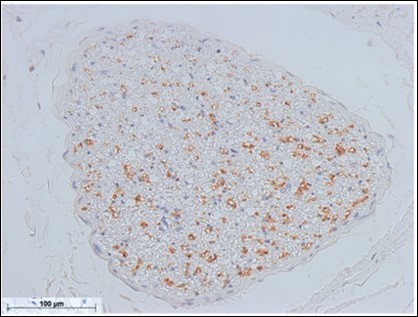

Figure 5.Sympathetic nerve fibers of the optic nerve (anterior facial nerve: TH staining) Bar = 100um

Figure 6.Sympathetic nerve fibers of the mandibular nerve (mental nerve: TH staining) Bar = 100um